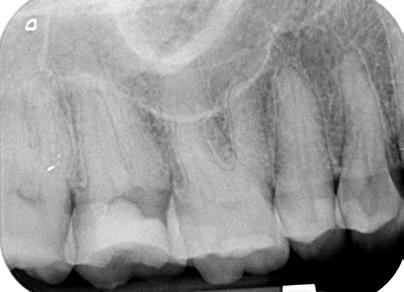

1. ábra: Kiindulási röntgen. A felső nagyőrlőfog trepanálását akut beavatkozásként egy másik rendelőben végezték.

5. ábra: Egyéves kontrollröntgen. – 6. ábra: Kiindulási felvétel. A mesiális irányba dőlt alsó első nagyőrlőfogat irreverzibilis pulpitissel diagnosztizáltuk, amely vélelmezhetően a disztális oldalán található parodontális lézióból indult ki. – 7. ábra: A posztoperatív felvételen látható, hogy a hozzáférési nyílás kialakítása a fog tengelyállásának megfelelő szögben történt.